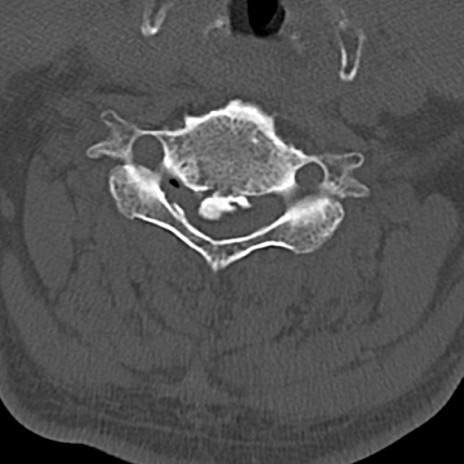

頚椎CT

横断像